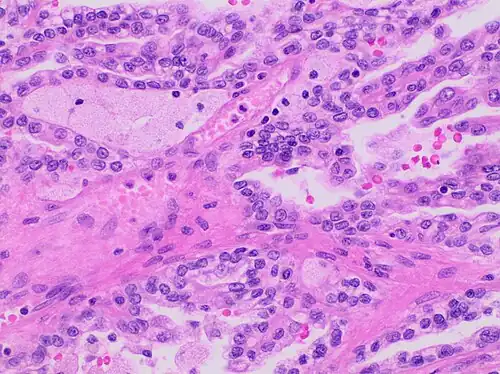

Papillary renal cell carcinoma, type 1, characterised by tubulopapillary architecture with admixed foamy histiocytes in the papillary cores.

Type 1 PRCC, also known as a renal tumor caused by a genetic predisposition of hereditary papillary renal cancer syndrome, compromises approximately 25% of all PRCCs.[14][15] In the perspective of immunochemistry, it has a profile of strong CK7 and alpha-methyl acyl-CoA racemase (AMACR) expression at most focal CA-IX expression.[16] Histologically, its epithelium is composed of relatively small-sized simple cuboidal cells lined in a single layer.[17] These cells are well-characterized by basophilic cytoplasm.[18] Due to its solid growth, an extremely compact papillary architecture is often observed.[16] Other morphological characteristics include intracellular hemosiderin and foamy macrophages placed inside of papillary fibrovascular cores or psammoma bodies.[19] In general, the nuclei of type 1 PRCC belong to grade 1-2 of the Fuhrman system.[16]